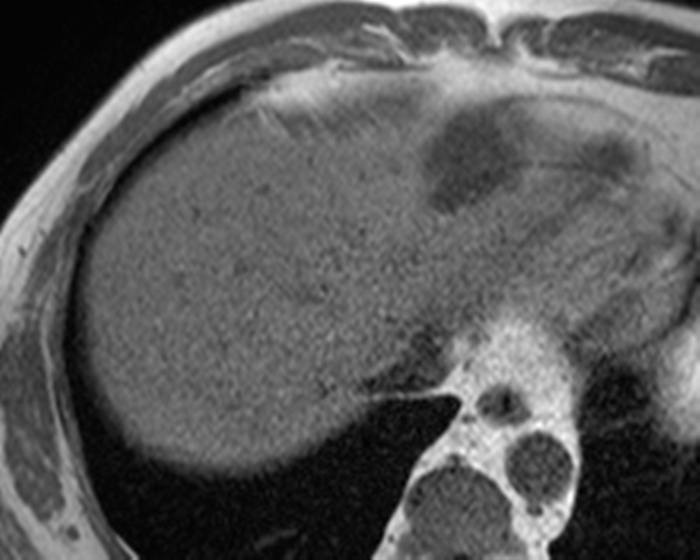

Ung thư đường mật

» Thông tin: Nam giới – 57 tuổi.

» Lâm sàng: Đau bụng.